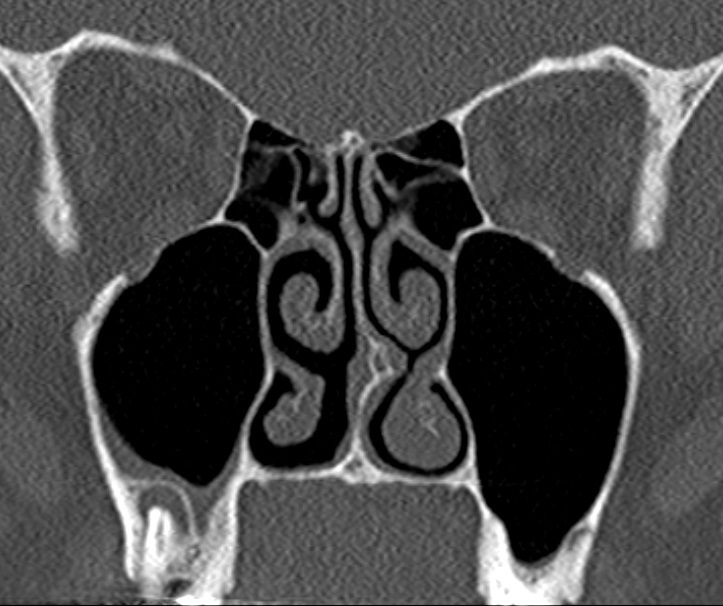

Le scanner est indispensable pour vérifier l’absence d’invasion osseuse du cancer et aussi pour vérifier l’absence de ganglions profonds qui n’auraient pas été palpés pendant l’examen clinique

Voici l’un des examens que vous récupérez.

Question 8 : Que pouvez-vous dire à partir de cette coupe ?

Elle apporte avec elle l’examen suivant, réalisé par son médecin traitant. Une petite masse fluctuante est palpée dans le vestibule supérieur droit.

Question 13 : Qu’en concluez-vous ?

On voit bien le granulome apical, et le sinus maxillaire qui est bien aéré immédiatement au-dessus. Ce n’est donc pas une sinusite aiguë

On se trouve ici dans le cas d’un réchauffement de foyer dentaire chronique. Le scanner montre bien le granulome apical (image hypodense autour de l’apex dentaire), et le tableau clinique est typique d’une infection dentaire supérieure. Comme tout abcès, le traitement est à la fois un drainage et une antibiothérapie. Ne pas oublier le soin dentaire dans les suites de l’épisode aigu pour éviter toute récidive.